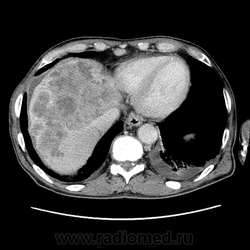

Печень. Процесс в средостении, бр.пол., забр.пр-ве. МСКТ.

Здравствуйте, коллеги! Мужчина около 70 лет. Жалобы: слабость, утомляемость около 3х месяцев, чувство тяжести на желудке после еды. Анамнез: онко не было. С вышеописанными жалобами обратился ко врачу, сделали ФГЭДС - признаки гастродуоденита, по биопсии - N. В течение 2х последних недель существенно похудел и начал желтеть. Выполнена МСКТ

Вероятно ГЦР, со всеми последствиями.

А как насчет холангиокарциномы с тромбозом воротной вены и мтс в средостение, лимфоузлы брюшной полости и забрюшинного пр-ва?

Я - за.

Внимательно пересмотрел, признаков характерных для ГЦР не нашел (кроме тромбоза). Согласен с холангиокарциномой, ещё бы отсроченную фазу, для печени минут через 12-15 .